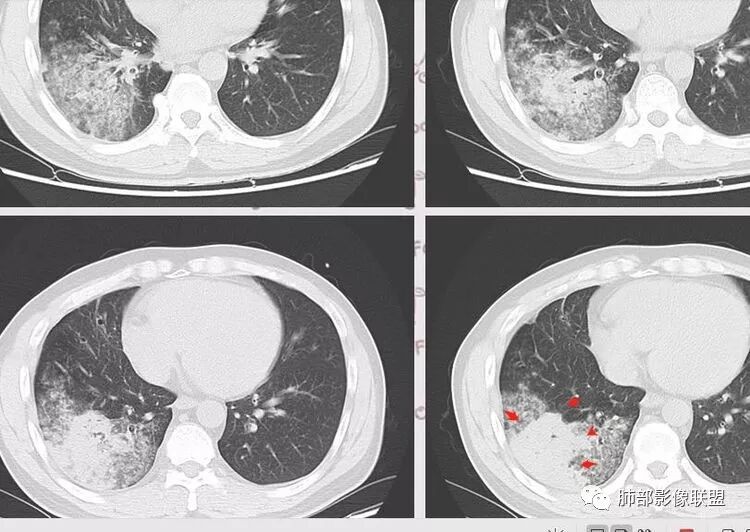

复查胸部CT视频显示肺部病灶明显吸收,淋巴结较前缩小。

患者在本院做了支气管镜,报告是有新生物,取了活检就转院了。病理结果是后来出来的。去肿瘤医院再做支气管镜,病理还是炎症。抗炎治疗(电话追问患者家属,具体不详)一个月后复查,右下肺病变基本吸收,肺门肿块明显变小;纵隔淋巴结基本都没了或者明显变小了

一个月吸收,不是快,是慢,合并机化可能。结核肯定不是。只是觉得你们早上不看病史。有点不好,至少抗感染复查。

现在看树雾,支原体有可能。只是淋巴结肿大和体重减低有迷惑性

如果TB不可能吸收这么快

对,支原体要考虑

定不到菌的,提示感染就足矣了,除非有很特异征像,体重减轻和这个病程是无关的,不要过度联系。

我一直以为是二元的,我觉得特别淋巴结里面又有钙化灶,我的想法肺部就是炎性病变,因为很典型的分布符合气道来源炎性病变,但是淋巴结是独立出来的,里面有钙化灶怀疑结核可能。

淋巴结同步缩小了,其实挺常见的

如果看片考虑二元论,肺部符合急性炎性病变特点。淋巴结真不好说,一元论还没想通,也有存在特异性的可能,比较少。我就这样分析的,写报告我会写二元,把淋巴结独立出来,把右下肺急性炎症独立出来。

这个病灶我犹豫很久,病史体重减轻,很不踏实,体重减轻到底什么原因?到底有无联系呢?一般提供病史,我们还是考虑联系,其实当时我个人还是倾向有联系的,常见慢性炎性病变消耗的和恶性肿瘤。

淋巴结肿大常见那么几种病变,转移瘤不符合,影像右下肺病变为炎性病变征象,前面已描述其特征:形态、走形、边缘(实质和GGO)、中央间质增厚、均匀强化、支气管充气征。都符合急性炎性病变。